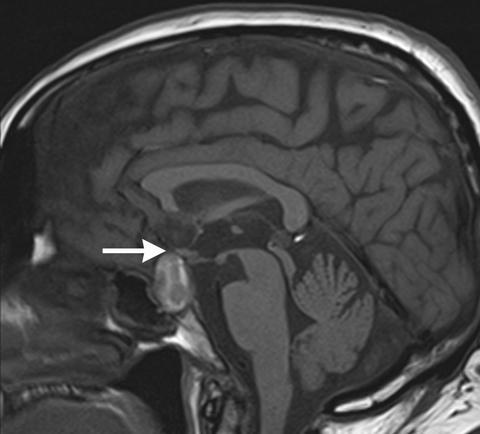

A 64-year-old woman with dilated right pupil, nausea, and headache